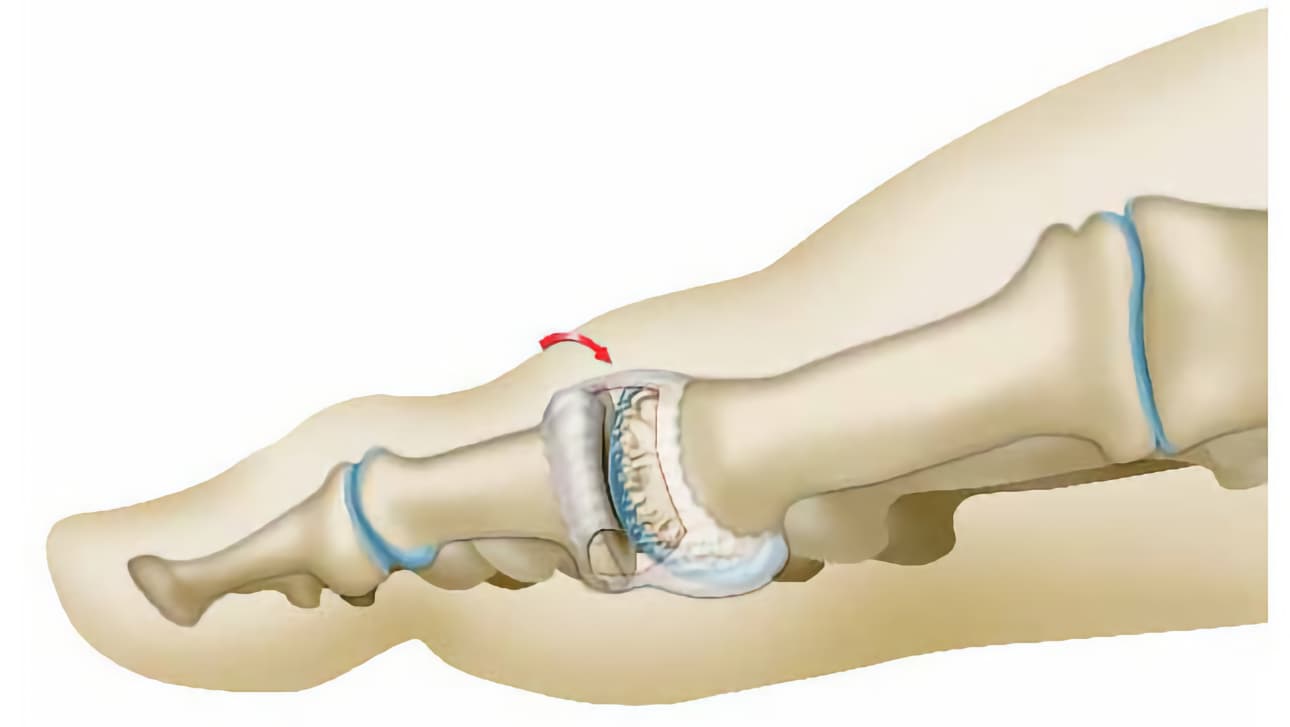

Σε ασθενείς νεαρής ηλικίας, στους οποίους ο χόνδρος δεν παρουσιάζει σοβαρές φθορές και τα οστά (μετατάρσιο και φάλαγγα) του μεγάλου δακτύλου είναι μακρύτερα σε σχέση με τα οστά των άλλων δακτύλων, προχωρεί σε οστεοτομία βράχυνσης. Πρόκειται για επέμβαση αφαίρεσης τμήματος του μεταταρσίου οστού, για να μικρύνει και να μην επιβαρύνεται η άρθρωση.

Ο χειρουργός, με τη χρήση ενός χειρουργικού πριονιού, κόβει και αφαιρεί ένα μικρό τμήμα του οστού (δύο ή τρία χιλιοστά). Στη συνέχεια, στερεώνει τα δύο τμήματα που απομένουν (με βελόνες, καρφίδες, βίδες ή πλάκες, ανάλογα με τις πρακτικές που εφαρμόζει).

Τον ίδιο τύπο επέμβασης μπορεί να εφαρμόσει και στη φάλαγγα. Εάν χρειαστεί, ο χειρουργός επεμβαίνει και στα δύο οστά. Η επέμβαση περιορίζει τον πόνο, μειώνοντας την πίεση, που ασκείται από τα δύο οστά στην άρθρωση.